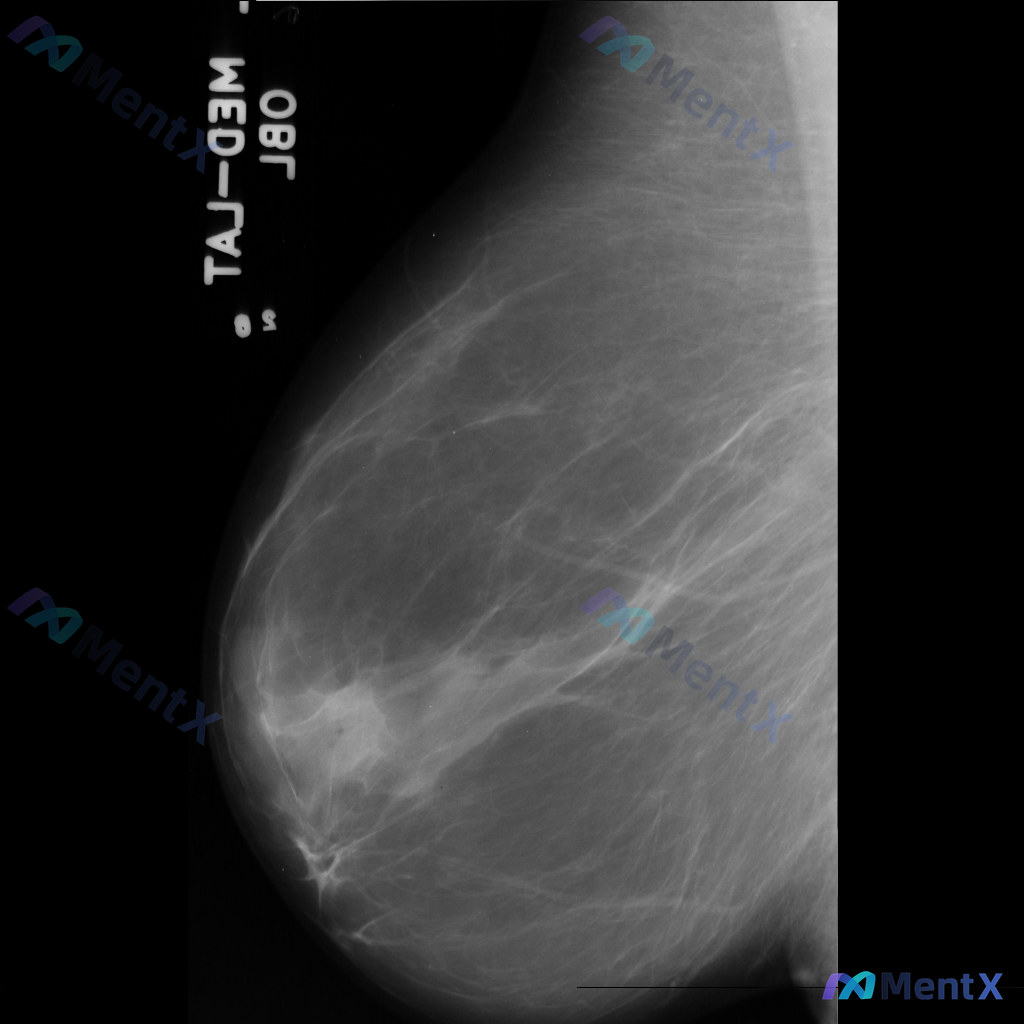

乳腺钼靶显示局灶性结构扭曲,大家觉得下一步更倾向考虑哪种情况?

整理到一份乳腺钼靶影像资料,主要表现如下:

- 乳腺中后部可见局灶性结构扭曲

- 无明确的肿块核心

- 周围腺体和脂肪界面被不规则牵拉

目前暂不提供既往影像对比和详细病史(手术史、外伤史、炎症史等)。